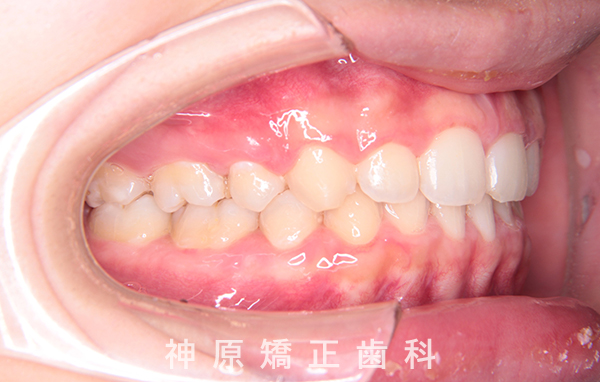

口元の突出感を改善するために小臼歯の抜歯が必要と判断しました。抜歯スペースを活用し、前歯を可能な限り後方へ移動させるため、上下に矯正用アンカースクリューを使用する計画です。患者様とご家族に十分な説明を行い、治療ゴールに同意を得た上で矯正治療を開始しました。矯正治療の結果、側貌はE-lineに調和したバランスの良い仕上がりとなりました。